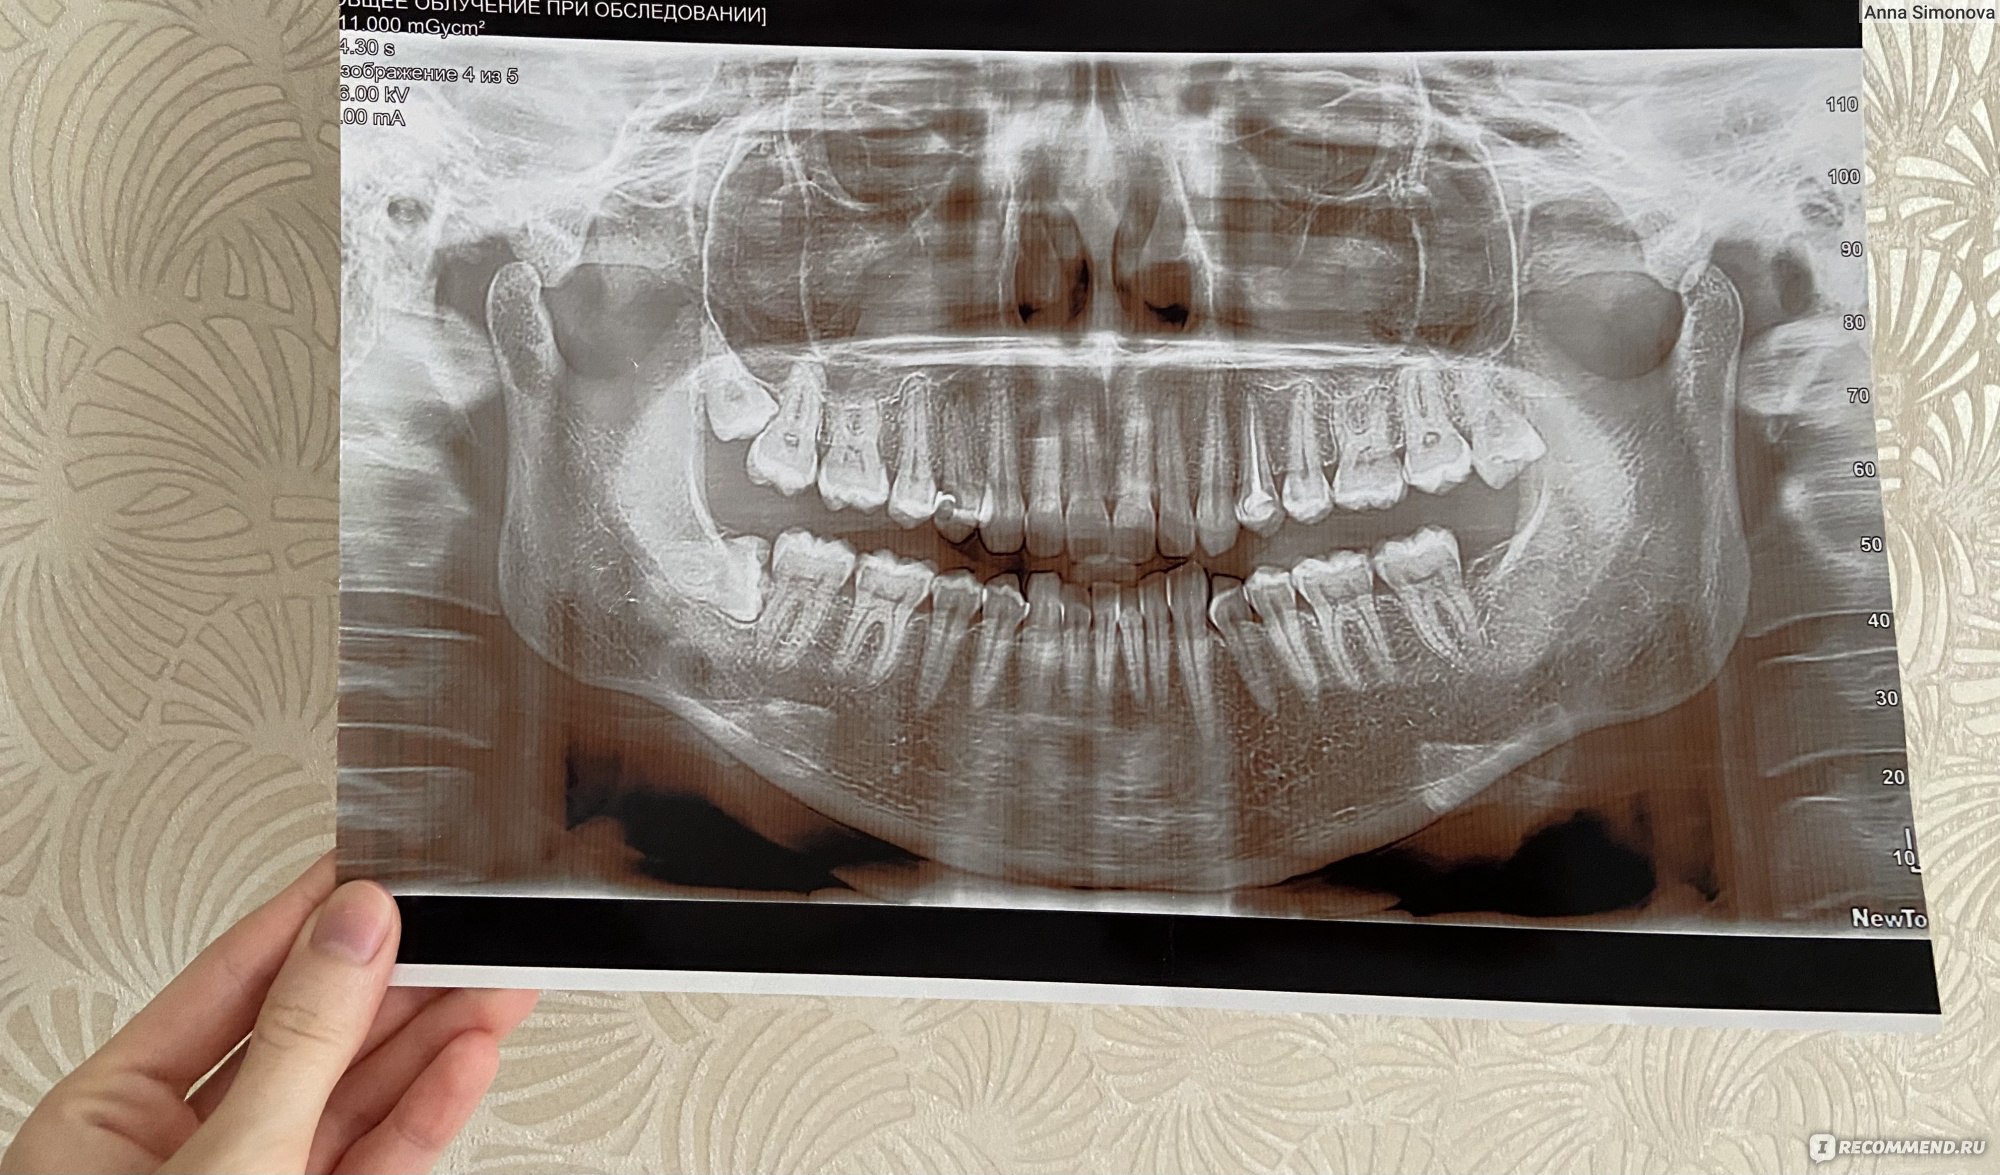

Фотографии ортопантомограмм и работ Родена